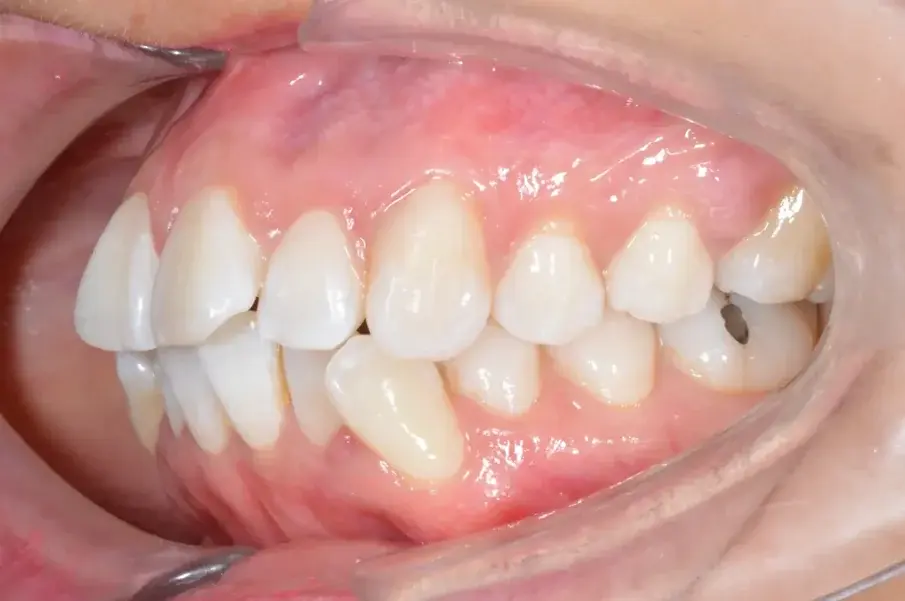

Фиг. 2а: Първоначални интраорални изображения.

Фиг. 2b: Първоначални интраорални изображения.

Фиг. 2c: Първоначални интраорални изображения.

35-годишна пациентка постъпва със струпване на зъби, болки в мускулите и ставите и главоболие след събуждане. При прегледа се установява I скелетен клас със струпване и бимаксиларна протрузия. Изследването на лицето показа конвексен профил с изпъкнали устни и квадратна форма на лицето, която се засилва при усмивка (фиг. 1-4). Тя съобщава за бруксизъм и се наблюдава двустранна хипертрофия на масетерите, но няма изменения в темпоромандибуларните стави.